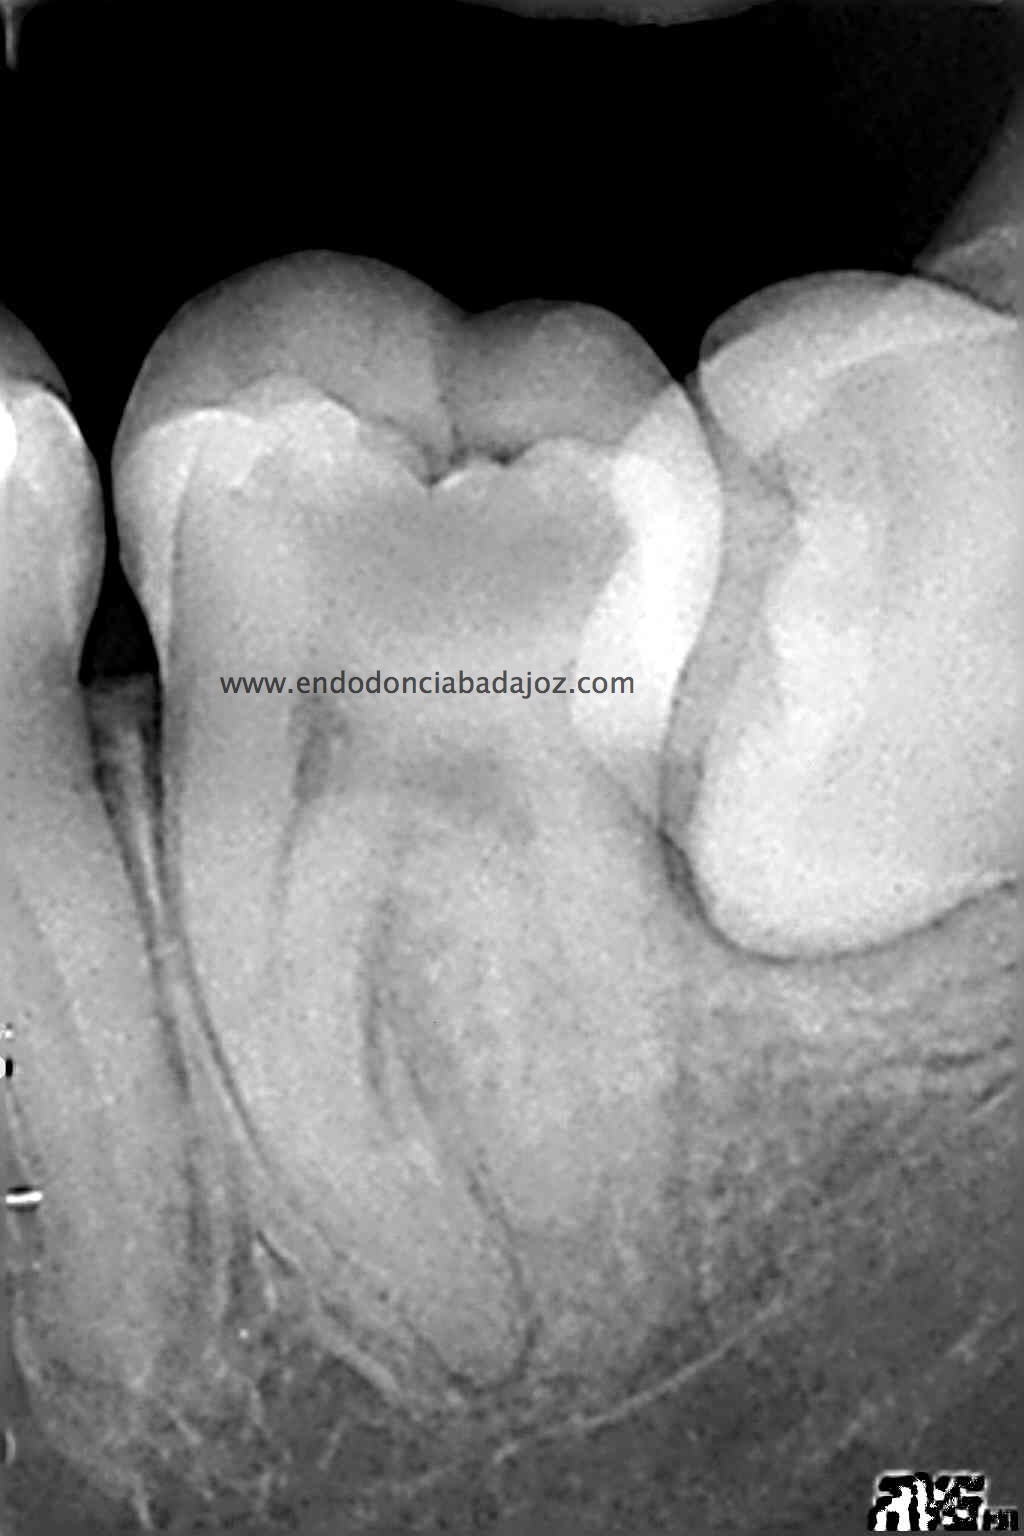

MOLAR INFERIOR CON 4 CONDUCTOS.

Se trata de un caso que ,a priori, traté como un 3.7 de tres conductos:

Después de haber instrumentado con un sistema Protaper, y habiendo estandarizado el conducto en un 25mm en apical y una conicidad del 6% con limas K3. observé que el conducto Distal presentaba otro conducto Disto-Vestibular cuya entrada estaba en la pared del conducto Disto-Lingual tratado, bastante complicado de trabajar.

Observando la Rx pude verificar y diferenciar las raices: